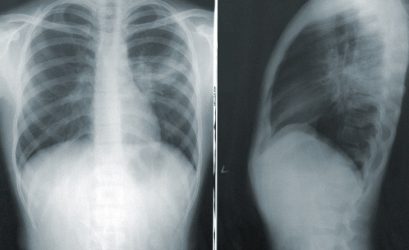

octubre 18, 2023VIENA.- Las mujeres no están suficientemente representadas en los estudios médicos que se usan para el diagnóstico y tratamiento de enfermedades pulmonares, hasta el punto de que no se tiene en cuenta cómo las dosis de […] [...]